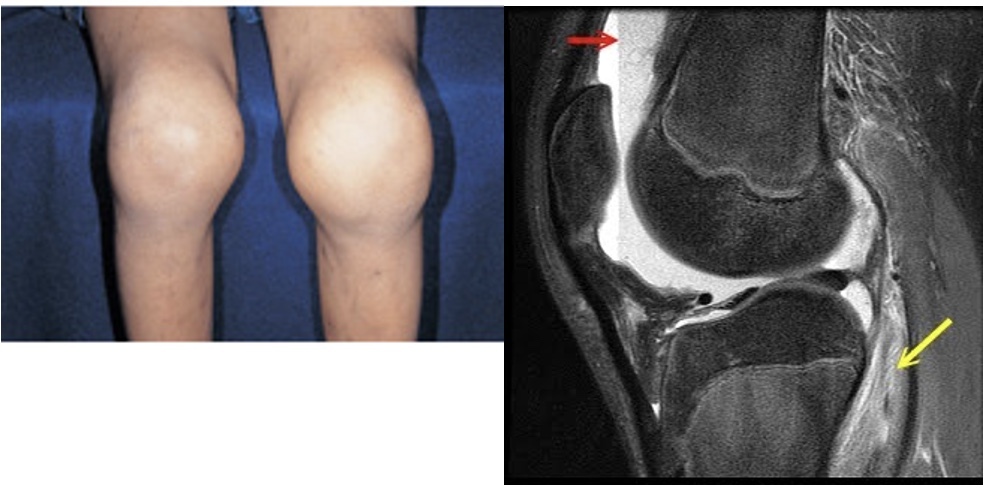

factor VIII deficiency w/ severe bleeding after trauma or surgery (into joints and muscles); PTT elevated

Hemophilia A

hemarthrosis (hemophilia A)